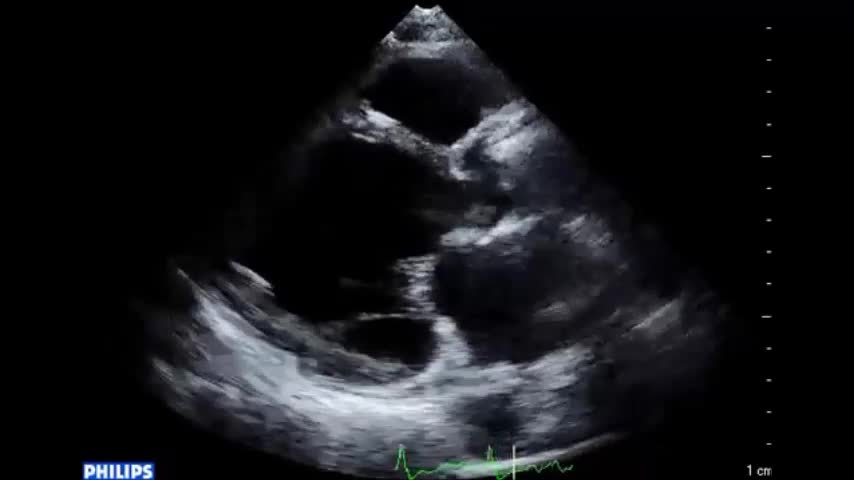

• 図5 心エコー、手術所見 a